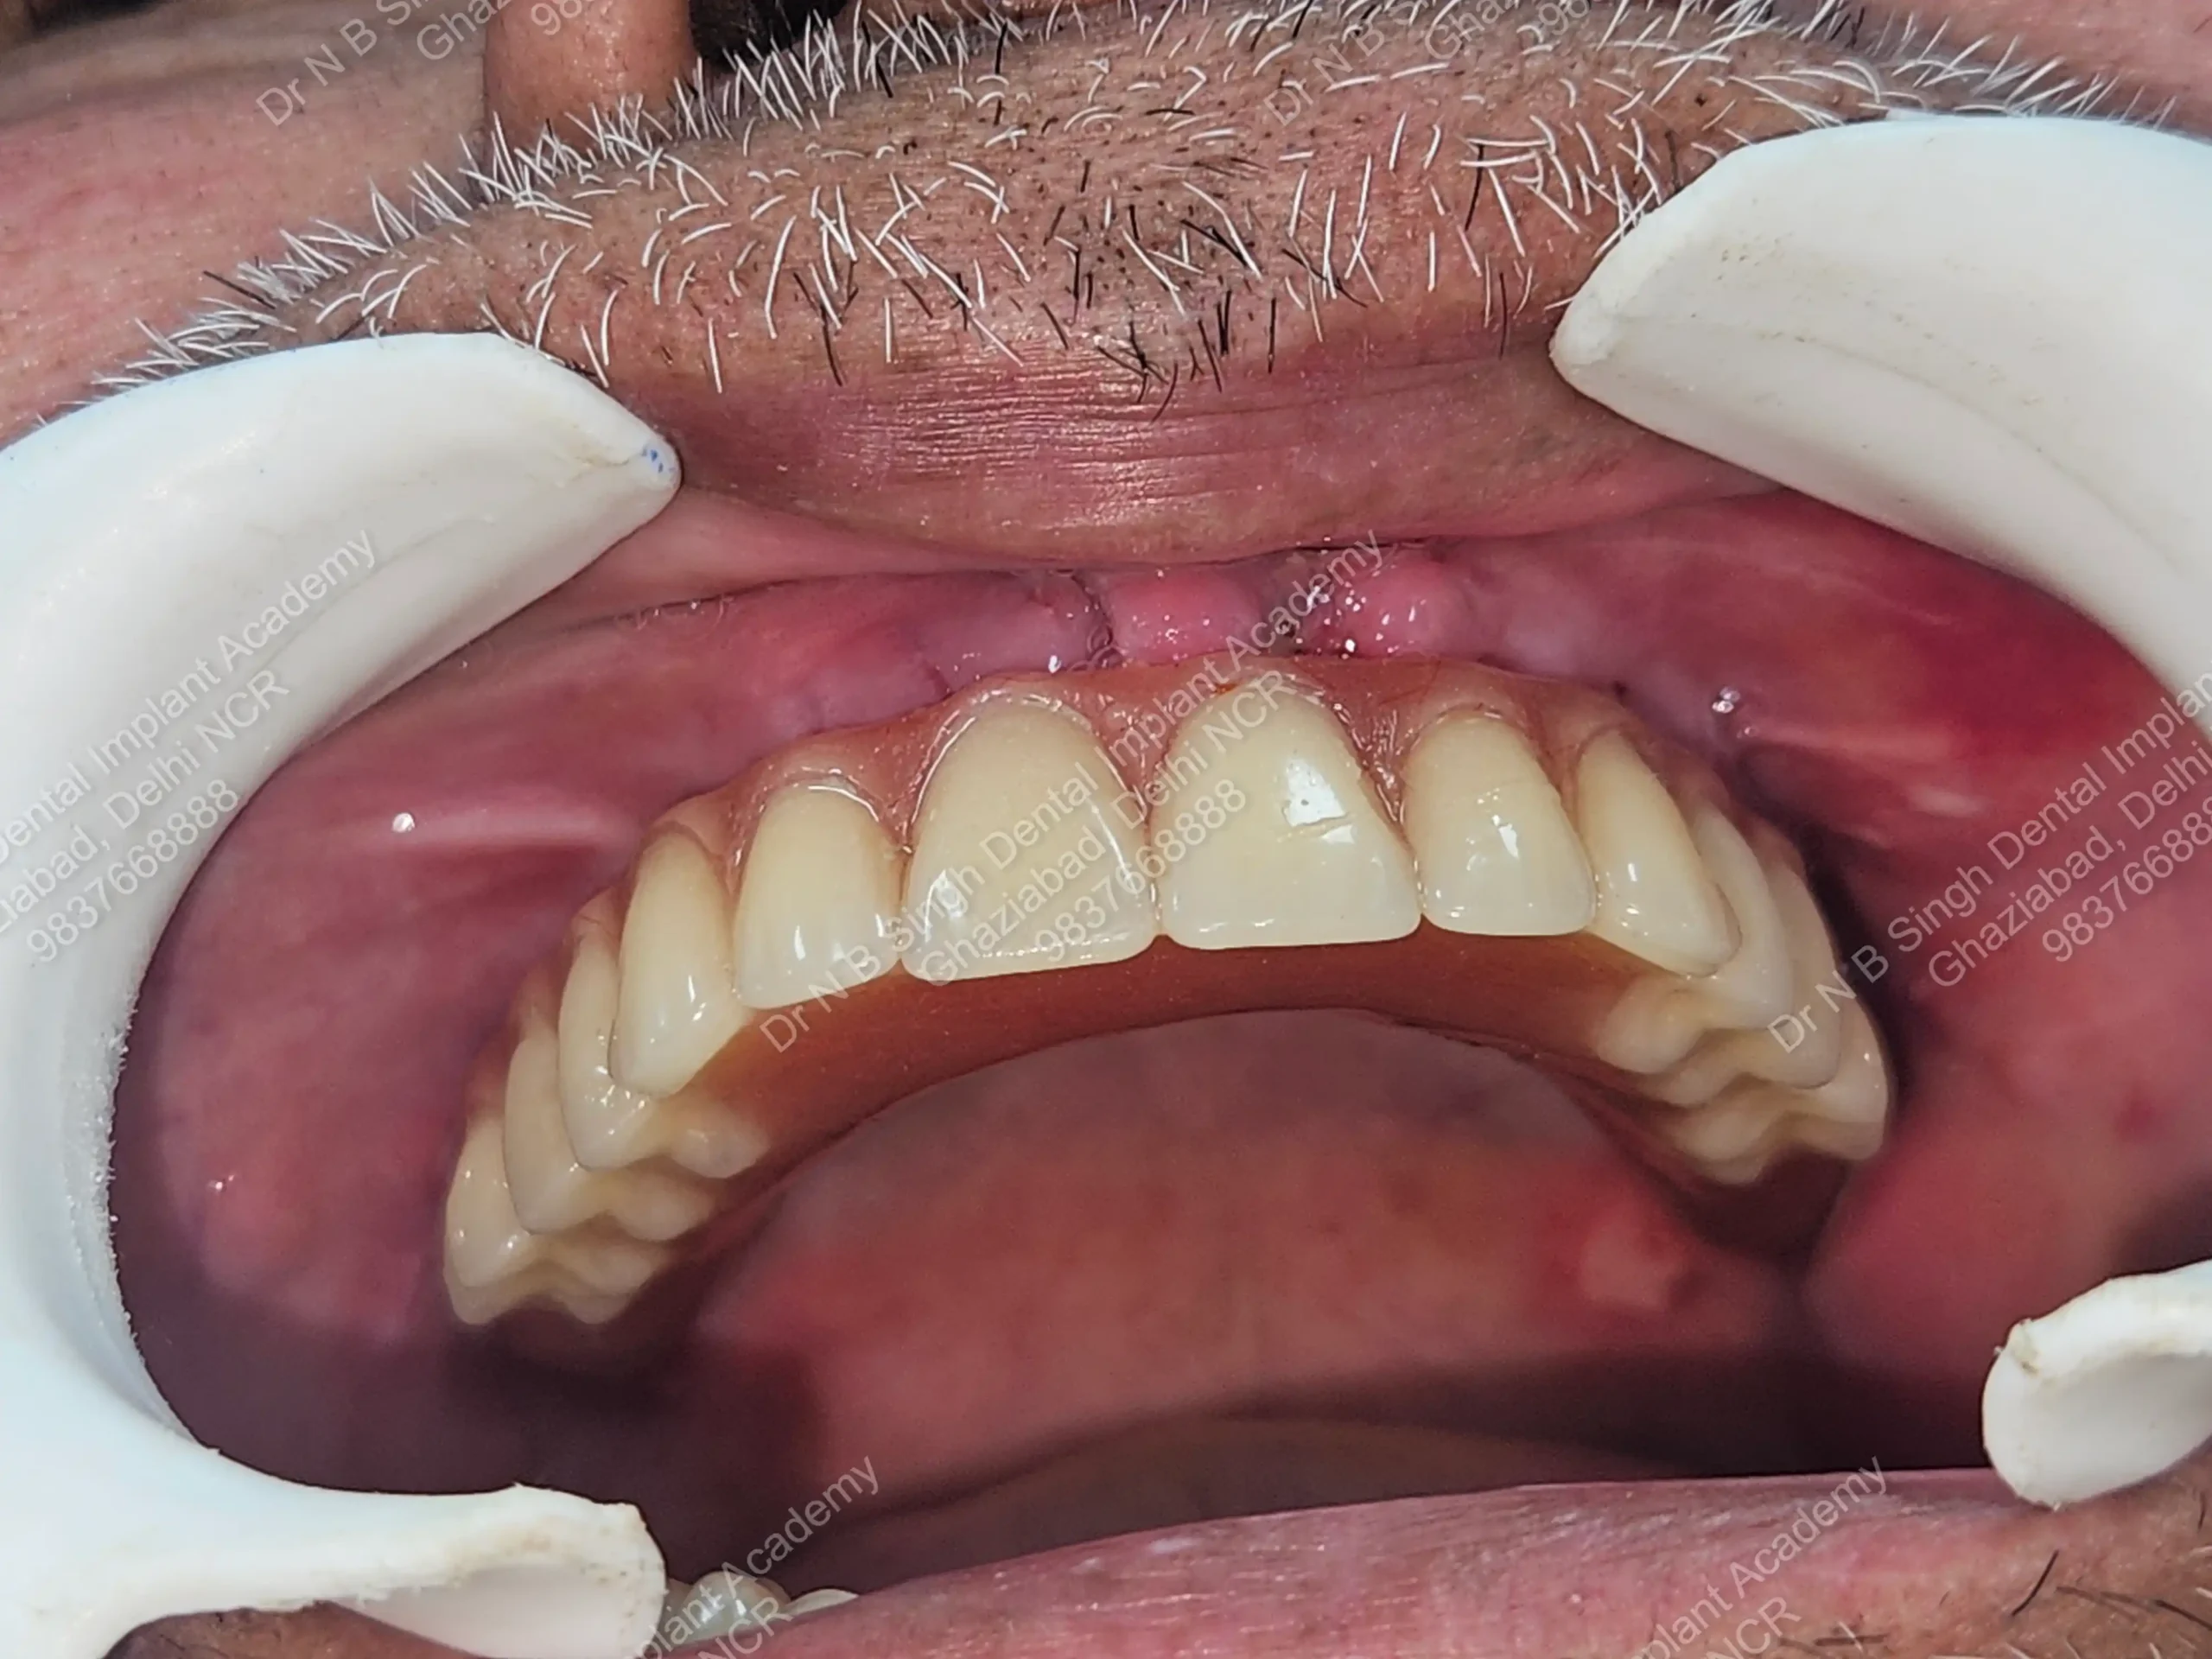

A008 Basal implants – af-qurs 1

Dr. N.B. Singh